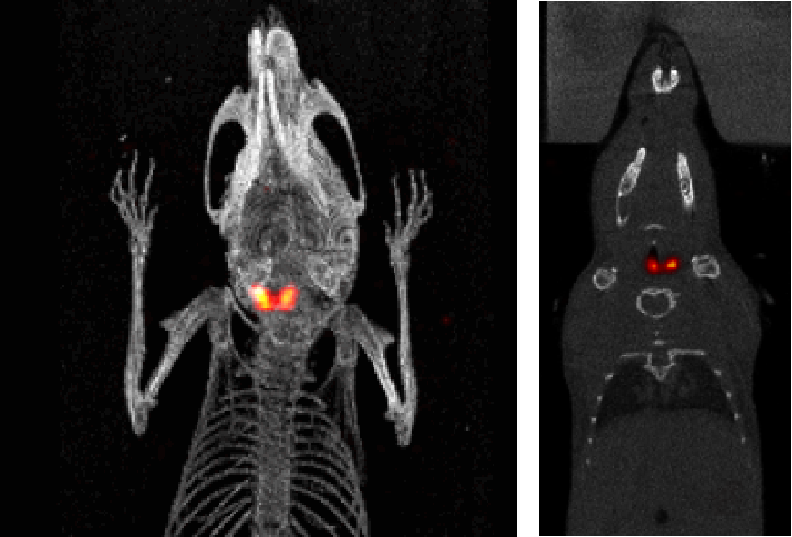

SPECT/CT組合圖像,小鼠的骨骼成像:99mTc-HDP,94.35MBq (2.55mCi) @ start acquisition,采集時間60min。

SPECT/CT組合圖像,大鼠的骨骼成像:99mTc-HDP,200MBq,采集時間45min。